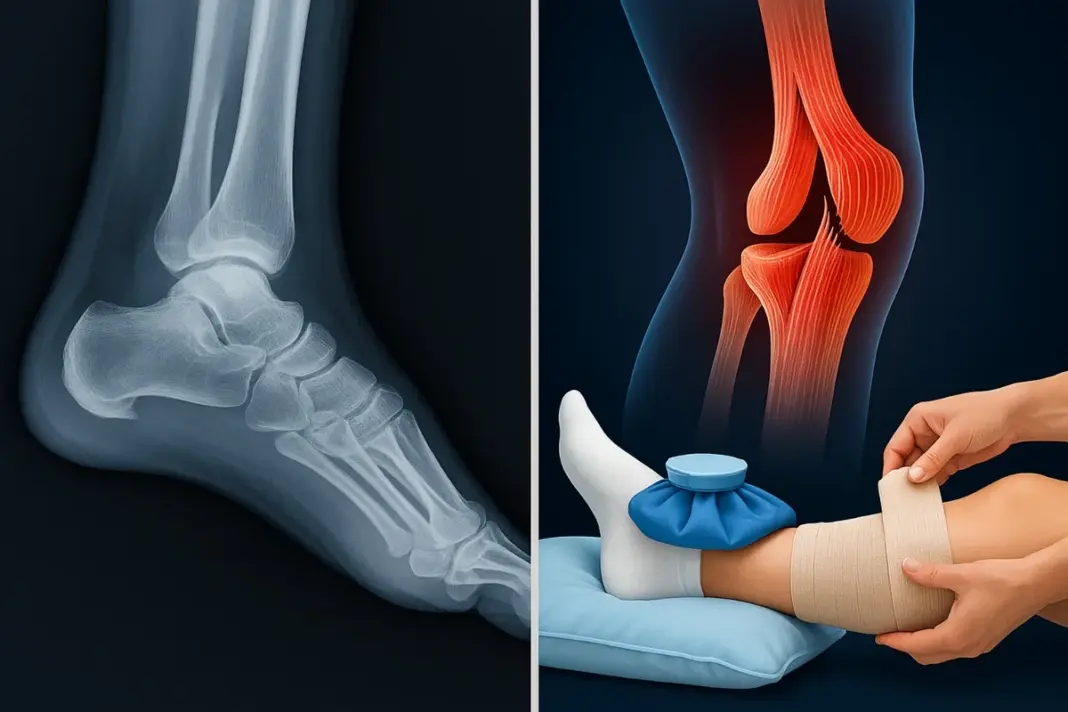

Dr Ankit Jose explains that fracture vs ligament rupture cases may share swelling and sudden pain, yet they behave differently from the very first moment. A fracture creates sharp pain that rises with every small touch or gentle move, and the person often cannot place weight on the limb. A visible deformity may appear when the break shifts bone alignment, and this makes quick imaging crucial.

Doctors depend on X-rays for clear fracture diagnosis and treatment, and this helps them plan the next step with confidence. A ligament rupture causes pain around the soft tissue near the joint, and movement may still be possible in many cases. Doctors check joint stability first and then use an MRI when they need to grade the tear before planning ligament rupture recovery tips.

RICE stands for rest, ice, compression, and elevation, the first defense against pain and swelling. Stopping activity gives bones and ligaments time to begin repair naturally. Ice applied for 15–20 minutes every hour soothes inflammation and numbs soreness. Compression using elastic bandages controls swelling but must not stop circulation.

Elevating the affected limb above heart level helps fluid drain away, easing pressure. Following RICE properly supports both fracture diagnosis and treatment phases and early ligament rupture recovery. When used early, it prevents stiffness and limits further tissue injury. Still, not every pain stops with RICE alone; some need deeper care.